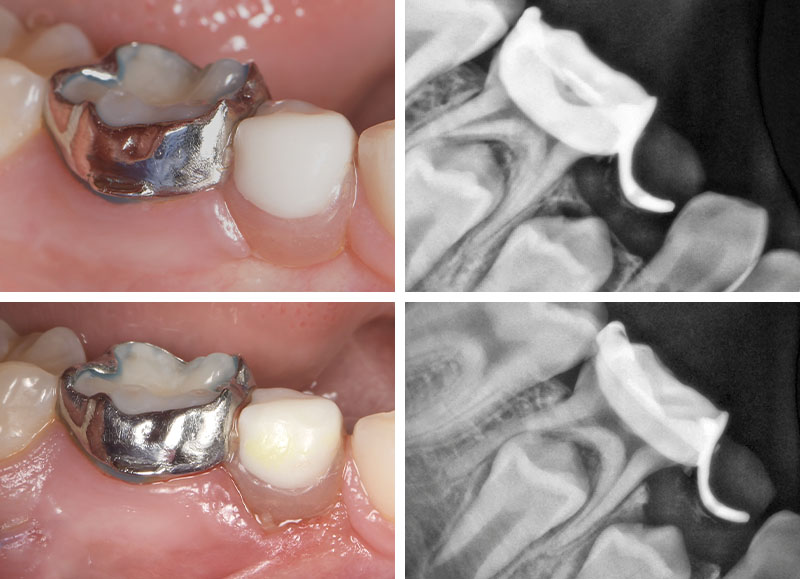

Fig. 05 : situation initiale.

Pour la mise en place, l’intrados a été préalablement sablé au laboratoire et le scellement a ici été réalisé avec du Transbond Plus Light Cureband Adhesive de 3M® qui contient du fluor, permettant la prévention des décalcifications.

Sa photopolymérisation permet aussi une mise en œuvre plus rapide avec moins de risque de contamination salivaire pendant le temps de prise. De plus, sa couleur bleue permet une élimination facile des excès. Enfin, les radios nous permettent de vérifier l’ajustage des bagues et les éventuels excès de Transbond.

Fig. 06 : scellement du mainteneur d’espace sur-mesure.